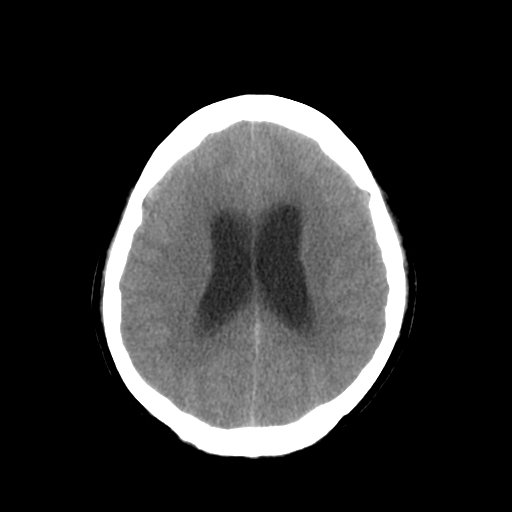

男,34岁,头痛数天。请大家看看是否有占位.

脑干、右侧桥臂及右侧小脑半球可见等低混杂密度影,环池部分闭塞,小脑上池及第四脑室受压移位、闭塞,考虑占位性病变可能性大,胶质瘤?室管膜瘤?不除外脑神经如听神经瘤及梗塞等,建议上传骨窗

脑干、右侧桥臂及右侧小脑半球可见等低混杂密度影。轻度脑积水。考虑右侧桥臂区域占位性病变。建议mri检查。

右侧桥小脑区见等混杂密度占位影,病变境界不清,环池部分闭塞,四脑室受压左移,建议上传增强或mr检查片...